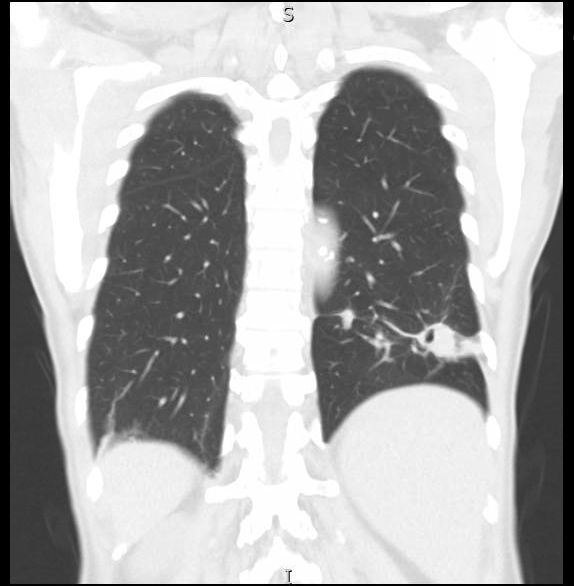

A 77 year-old male who immigrated from India at twenty years of age, with history of polycythemia vera, initially presented with hoarseness, occasional non-productive cough, weight loss and night sweats for two months. Of note, he is a non-smoker with no recollection of significant inhalational exposure. A chest x-ray (CXR) showed left lower lobe (LLL) consolidative changes. A subsequent computed tomography (CT) of the chest with contrast demonstrated a 2.4cm x 6.3cm nodular cavitary lesion within the LLL with adjacent smaller nodules within the parenchyma. A positron emission tomography (PET) scan correlated with a LLL fluorodeoxyglucose (FDG) avid mass. The working diagnosis at this time was malignancy. Approximately one month after, he underwent bronchoscopy with navigation – where brush and forceps biopsies and bronchoalveolar lavage (BAL) were performed. The results were negative for malignancy, contrary to the main diagnosis. Acid-fast bacillus smear was also negative. He was followed up with two serial CT chests done two months apart which showed no significant change. Finally, he underwent video assisted thoracoscopic surgery (VATS) with wedge resection of the LLL and chest tube placement. The postoperative course was complicated by heavy bleeding from the chest tube requiring surgical exploration and control of the bleeding. He was discharged on day five of admission.

Interestingly, the pathology revealed multiple necrotizing granulomata and focal emphysematous changes. The gram stain and mucicarmine stains were positive in yeast form consistent with Cryptococcus. Serum cryptococcal antigen sent subsequently, also returned positive at titers 1:8. Lumbar puncture was negative for central nervous system infection. The decision was made to place the patient on a six month course of fluconazole which is currently ongoing. Upon further interrogation, he endorsed living on a farm in India before emigration.